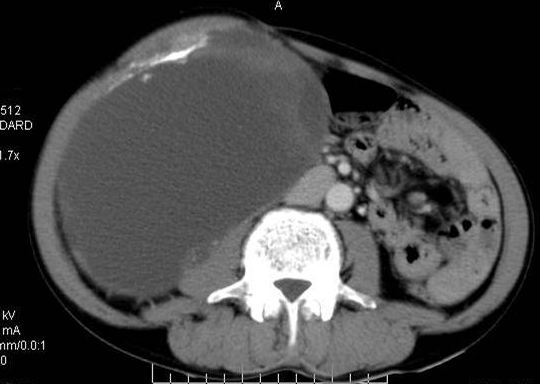

动脉期